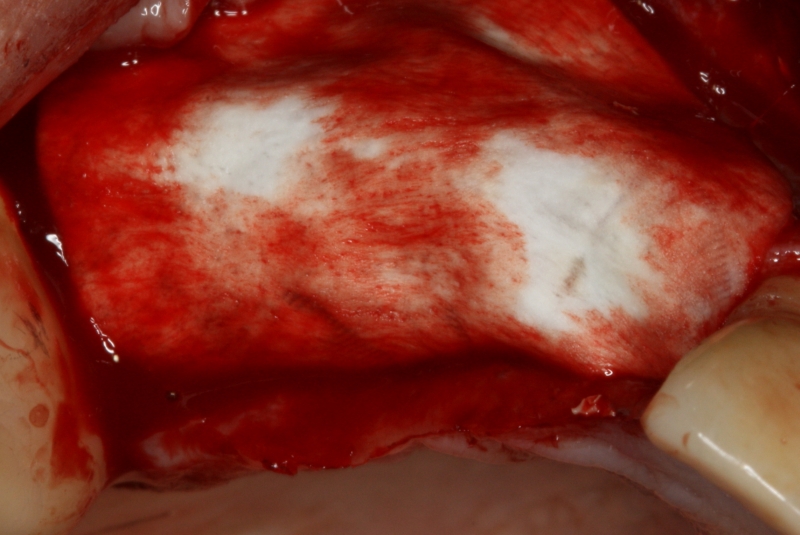

GBR and soft tissue augmentation with cerabone® and mucoderm® - H. Maghaireh & V. Ivancheva

Initial situation: missing teeth #11 & 12 and badly broken #21 root